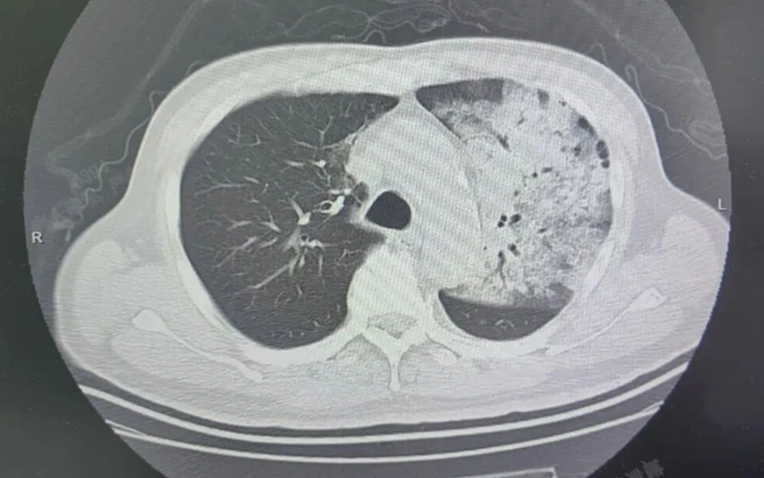

Sau khoảng một tuần điều trị tại bệnh viện địa phương, bệnh tình của ông đột ngột xấu đi. Bệnh nhân bắt đầu khó thở, rối loạn ý thức. Kết quả chụp CT cho thấy 2 phổi bị nhiễm trùng nặng, gần như “trắng xóa”. Dù đã được hỗ trợ thở máy nhưng tình trạng oxy máu vẫn không cải thiện.

Người đàn ông sốt 40 độ C, phổi gần như “trắng xóa”, chỉ vài ngày đã suy đa tạng: Thủ phạm liên quan đến thói quen nhiều gia đình vẫn mắc - Ảnh 1.